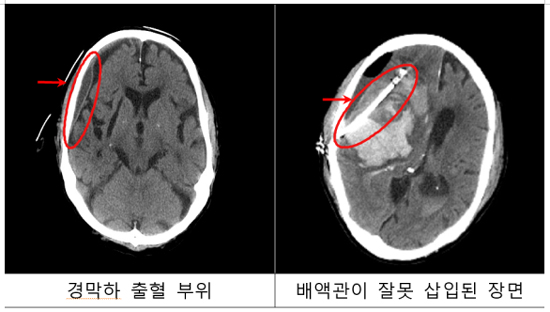

- 진단 및 평가: CT 또는 MRI 스캔을 통해 출혈의 위치, 정도 및 환자의 전반적인 상태를 파악합니다.

- 수술: 상황에 따라 출혈을 제거하고, 필요한 경우 뇌의 압력을 줄이기 위한 수술을 시행합니다.